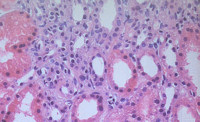

Carcinoma renal de ductos colectores de Bellini

Helena Pérez Berenguer ( 1) , Fca. Maria Peiró Marques ( 2 ) , Alicia Gómez Tierno ( 2 ) , Gonzalo Ariel Guarda( 2 )

Cuerpos de PML en nefropatía IgA en paciente con VIH

Waleska Salcedo Mercado, Alejandro Parra Cubillos, Roxana Elizabeth Sánchez Pacheco, Clara Caballero, Javier Gómez Román

NEFROPATÍA POR OXALATO. PRESENTACIÓN DE UN CASO Y REVISIÓN BIBLIOGRÁFICA

Mejía U, E., Cuesta Rosero, D.S., Alfaro Torres, J., Vicente Arregui, S., Alastuey Aisa, M., Torrecilla Idoipe, N, Valero Torres, A.